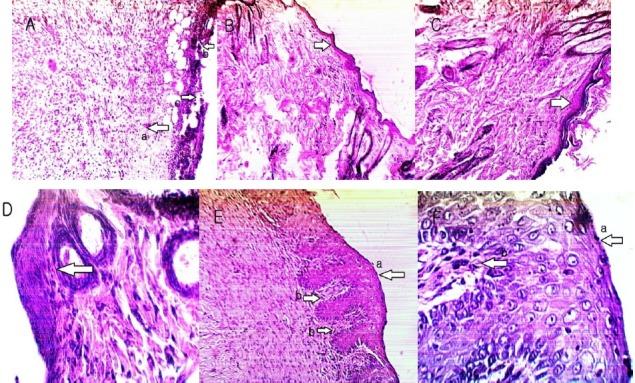

Evaluation of phytochemicals, antioxidant and burn wound healing activities of Duchesne fruit peel.

Iran J Basic Med Sci. 2017 Jul;20(7):798-805. doi: 10.22038/IJBMS.2017.9015.